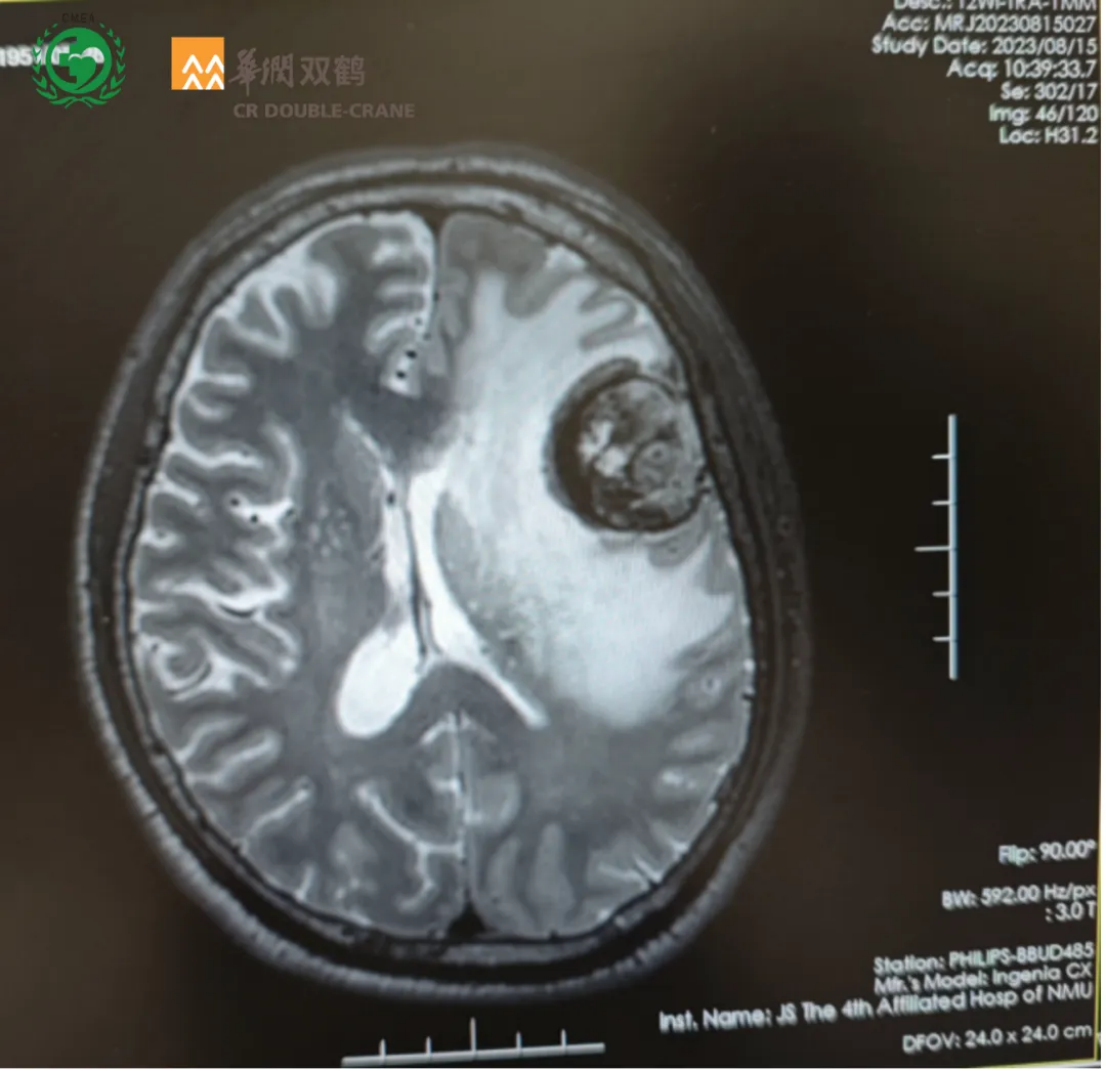

2023-08-15复查磁共振平扫+增强提示:左侧额叶占位性病变,大小约3.8cm*3.2cm *3.5cm团块状异常信号影,结合病史,考虑脑转移瘤;脑内多发缺血腔梗灶;老年性脑改变(图1)。

图1 复查磁共振平扫+增强